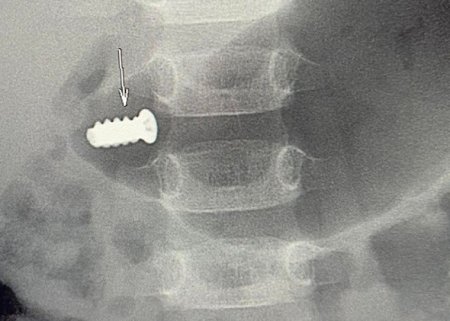

“Üç yaşlı uşaq evdə şurup qırığını götürüb burnuna daxil edib, metal yad cisim burun-udlaqdan qida borusuna, oradan da mədəyə keçib. Mədənin metal yad cismi”, - deyə həkim qeyd edib.